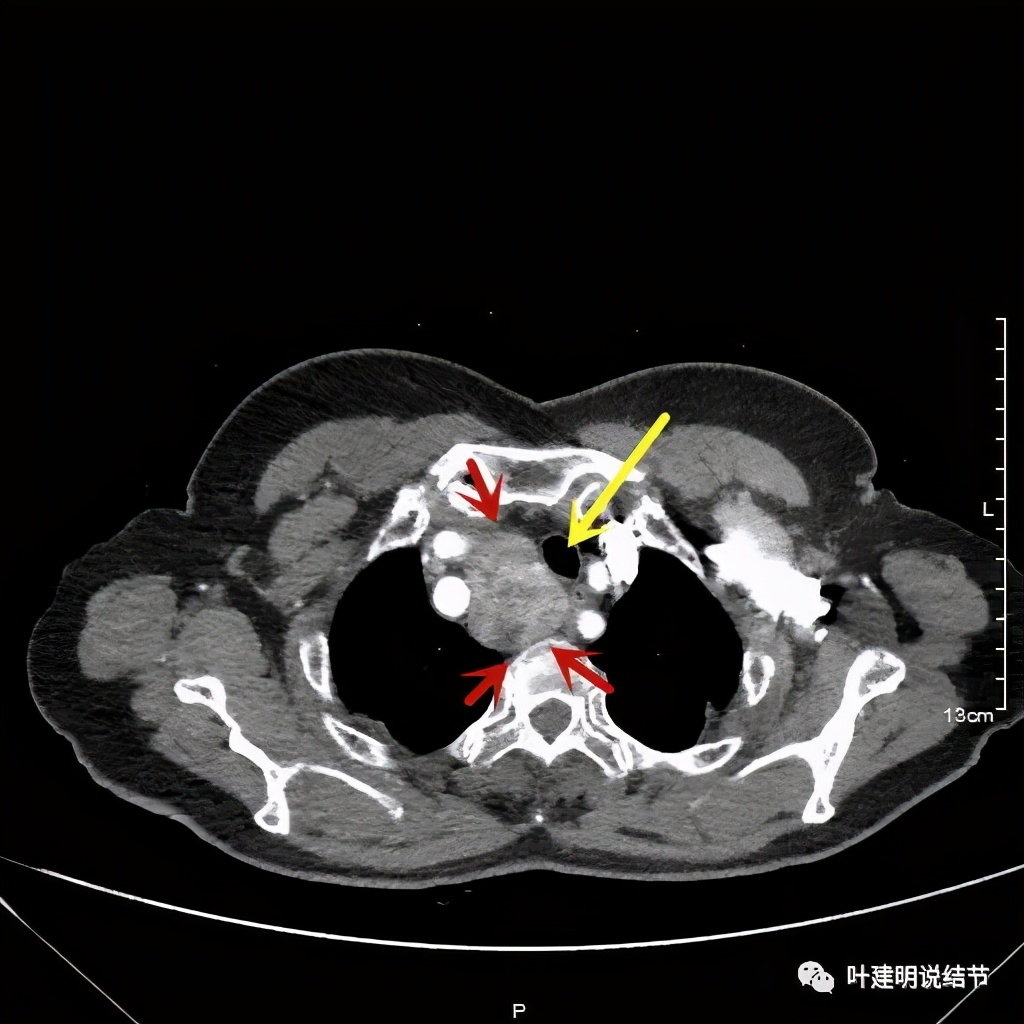

金华地区的某A,今年已经76岁了,近段时间觉得胸闷不适,还有刺激性咳嗽,总是不会好,到当地医院查了胸部CT,发现是纵隔肿瘤。当地医生建议她到金华市中心医院做下气管镜下穿刺活检,以明确肿瘤性质。因为认识我们医院的某外科主任,所以又建议她来找我,结果我一看她从当地带来的片子,是纵隔内巨大的占位,与气管关系密切,位于气管右侧、食管右前侧、上腔静脉左侧、无名静脉后侧,被诸多结构包绕着,而且肿瘤密度不均,靠气管与无名静脉侧间隙不清,首先考虑纵隔内恶性或交界性肿瘤,由于年纪这么大,手术风险较高,若与气管有侵犯,则手术达不到根治,我也觉得应该先行经气管镜下的穿刺活检,明确病理后再考虑怎么办。所以让某A住到呼吸内科去,打算行气管镜下纵隔肿瘤穿刺活检。因当地的片子扫到胸顶部为止,没有做增强,我们先取本院增强片子上达胸顶,下达肿瘤下缘的范围来看看肿瘤的样子:

胸顶就开始有肿瘤了,黄色示受压迫移位的气管,红色示肿瘤